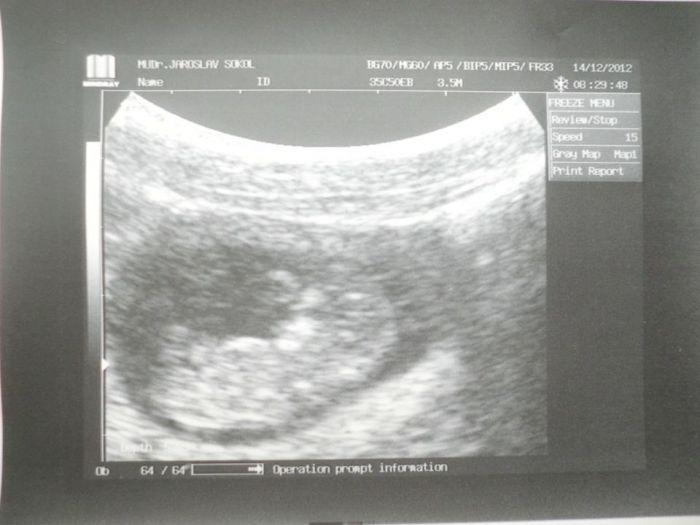

Přikládám fotku naší Pecičky z páteční kontroly, tj. 10+5ttVšem nastávajícím maminkám přeji hodně štěstí a zdraví!!!